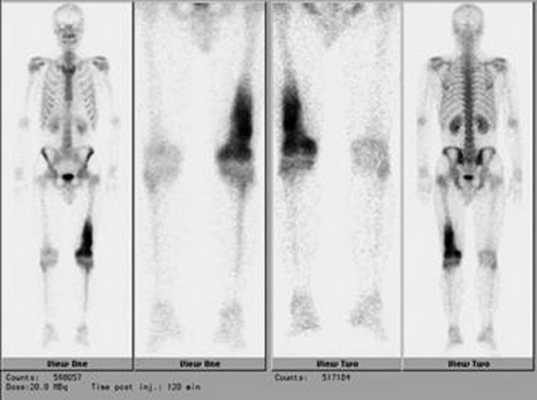

Планарная сцинтиграфия дает возможность определить распространенность опухоли по длине кости, а также выявляет отдаленные метастазы остеосаркомы в скелете (рис. 5).

Рис. 5. Радиоизотопное исследование скелета при саркомах костей